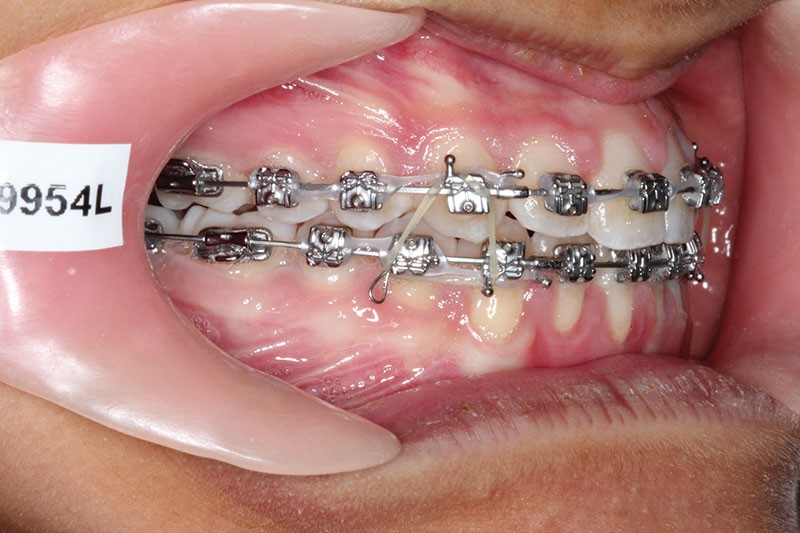

1re phase : recul des secteurs latéraux mandibulaires avec le Motion Classe III Carriere (fig. 4 à 6)

Nous mettons en place des bras latéraux Motion associés à des élastiques intermaxillaires ancrés sur des brackets sur 17 et 27 et une gouttière thermoformée maxillaire portée jour et nuit :

• 1er mois : élastiques 6 oz. 1/4”

• 2e mois et suivants : élastiques 6 oz.1/4“

L’objectif de cette étape est d’obtenir un recul des secteurs latéraux mandibulaires afin de positionner les molaires et canines en classe I et de réorienter le plan d’occlusion en haut en avant.